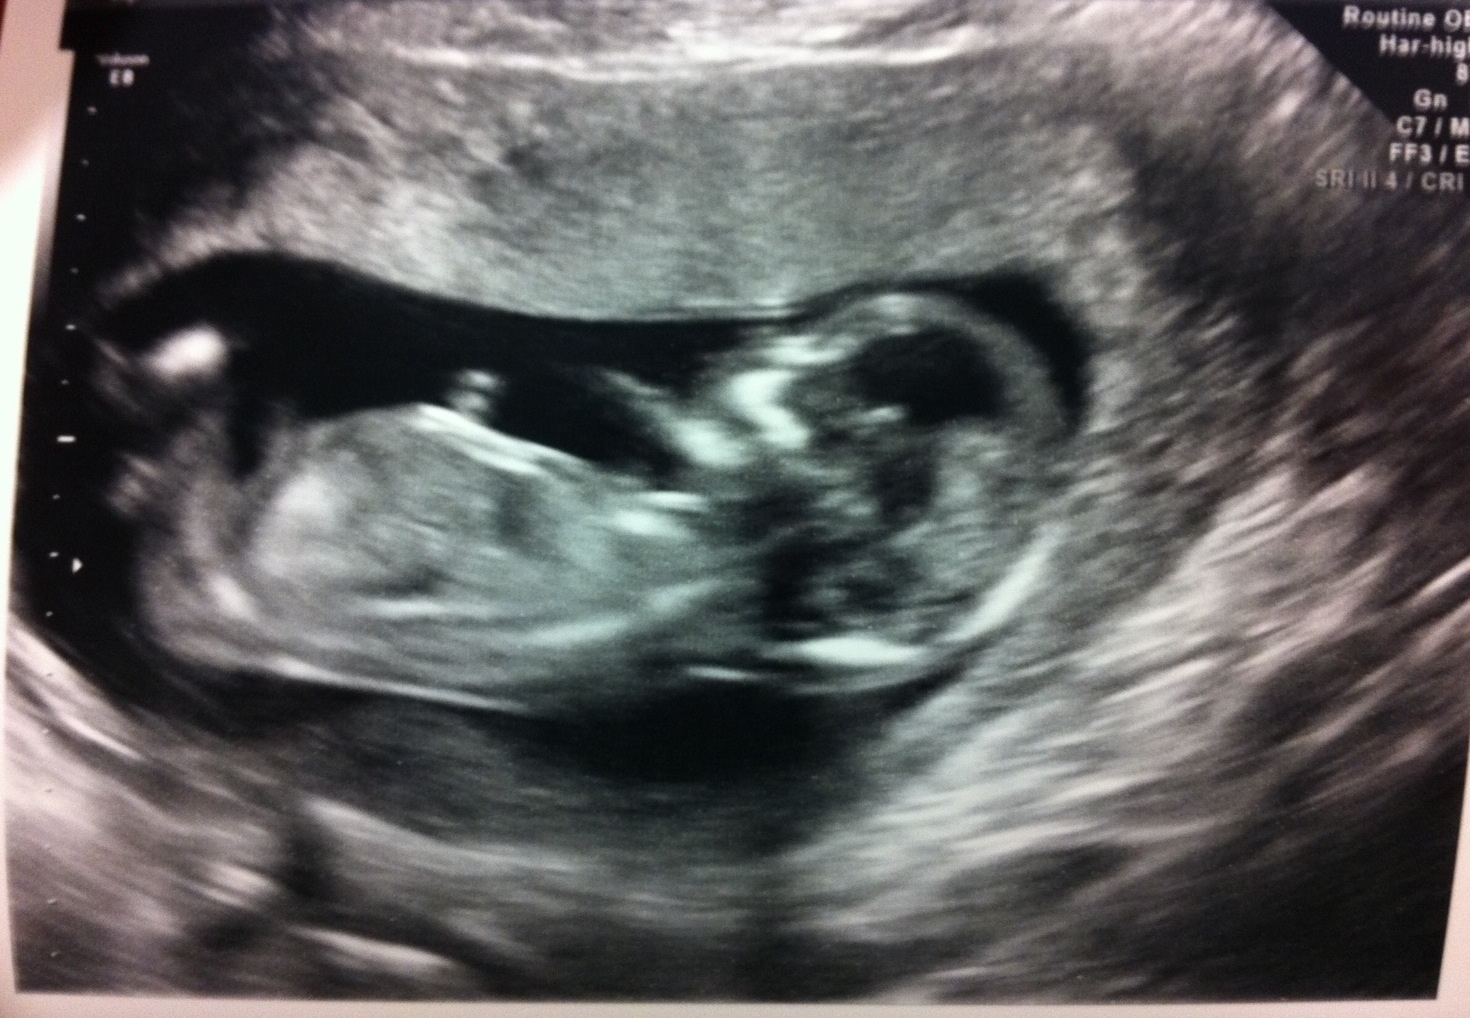

Here's another one. :)

I can't see a nub and I'm unsure of the potty shot, it kind of looks boyish but could be a girl, I can see where it looks a bit like three bits too. Not sure how your baby will develop and change in the next few weeks. Do you have any clear nub shots?

Maybe a boy, but you really need to see different

shots (potty and nub) to tell more accurately.